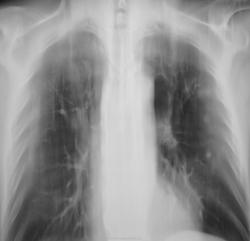

Инфицированные МБТ заполненные ретенционные бронхиальные кисты легких. Не исключаю, что фтизиатры обозначили эти изменения как множественные туберкулёмы. Имеется положительная динамика. С уважением Nikolas

В областной конторе не мудрствуя лукаво выставили инфильтративный (возможно, практически это верно). А, Вам часто приходилось видеть такое инфицирование ретенционных кист МБТ. У меня, это второй случай, за всю лучевую практику.

Лечили в ОПТД, как инфильтративный туберкулёз по полной стандартной программе.

Да, по первому КТ, это было заподозрено (мальформация). КТ за весь промежуток времени делали трижды. Потом, ретроспективно, собрав все в кучу, в том числе, и "флюшечный архив" - осенило...

В нашем случае, весь джентельменский набор, вплоть до МБТ.

Неоднократно обнаруженные "палки" всеми методами свидетельствуют, что "палки" есть...

Иногда, картина в динамике (скиалогическая), после курса (курсов) специфической терапии, говорит о многом...